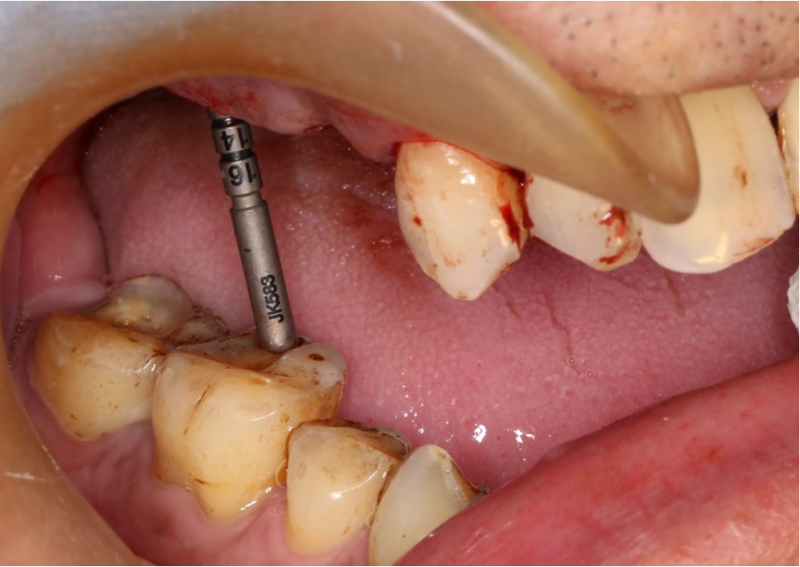

®按照術前方案進行備洞及植體植入,醫(yī)生可以通過屏幕軟件引導對手術中植入點、角度、深度實時追蹤

®對植體深度及方向進行確認

®完成3顆植體的植入,植體位點如術前方案設計,均在同軸線。

®多顆植體位點及角度的精確性,確保后期修復方案順利完成,也使患者能在使用過程中承受最佳的咬合力